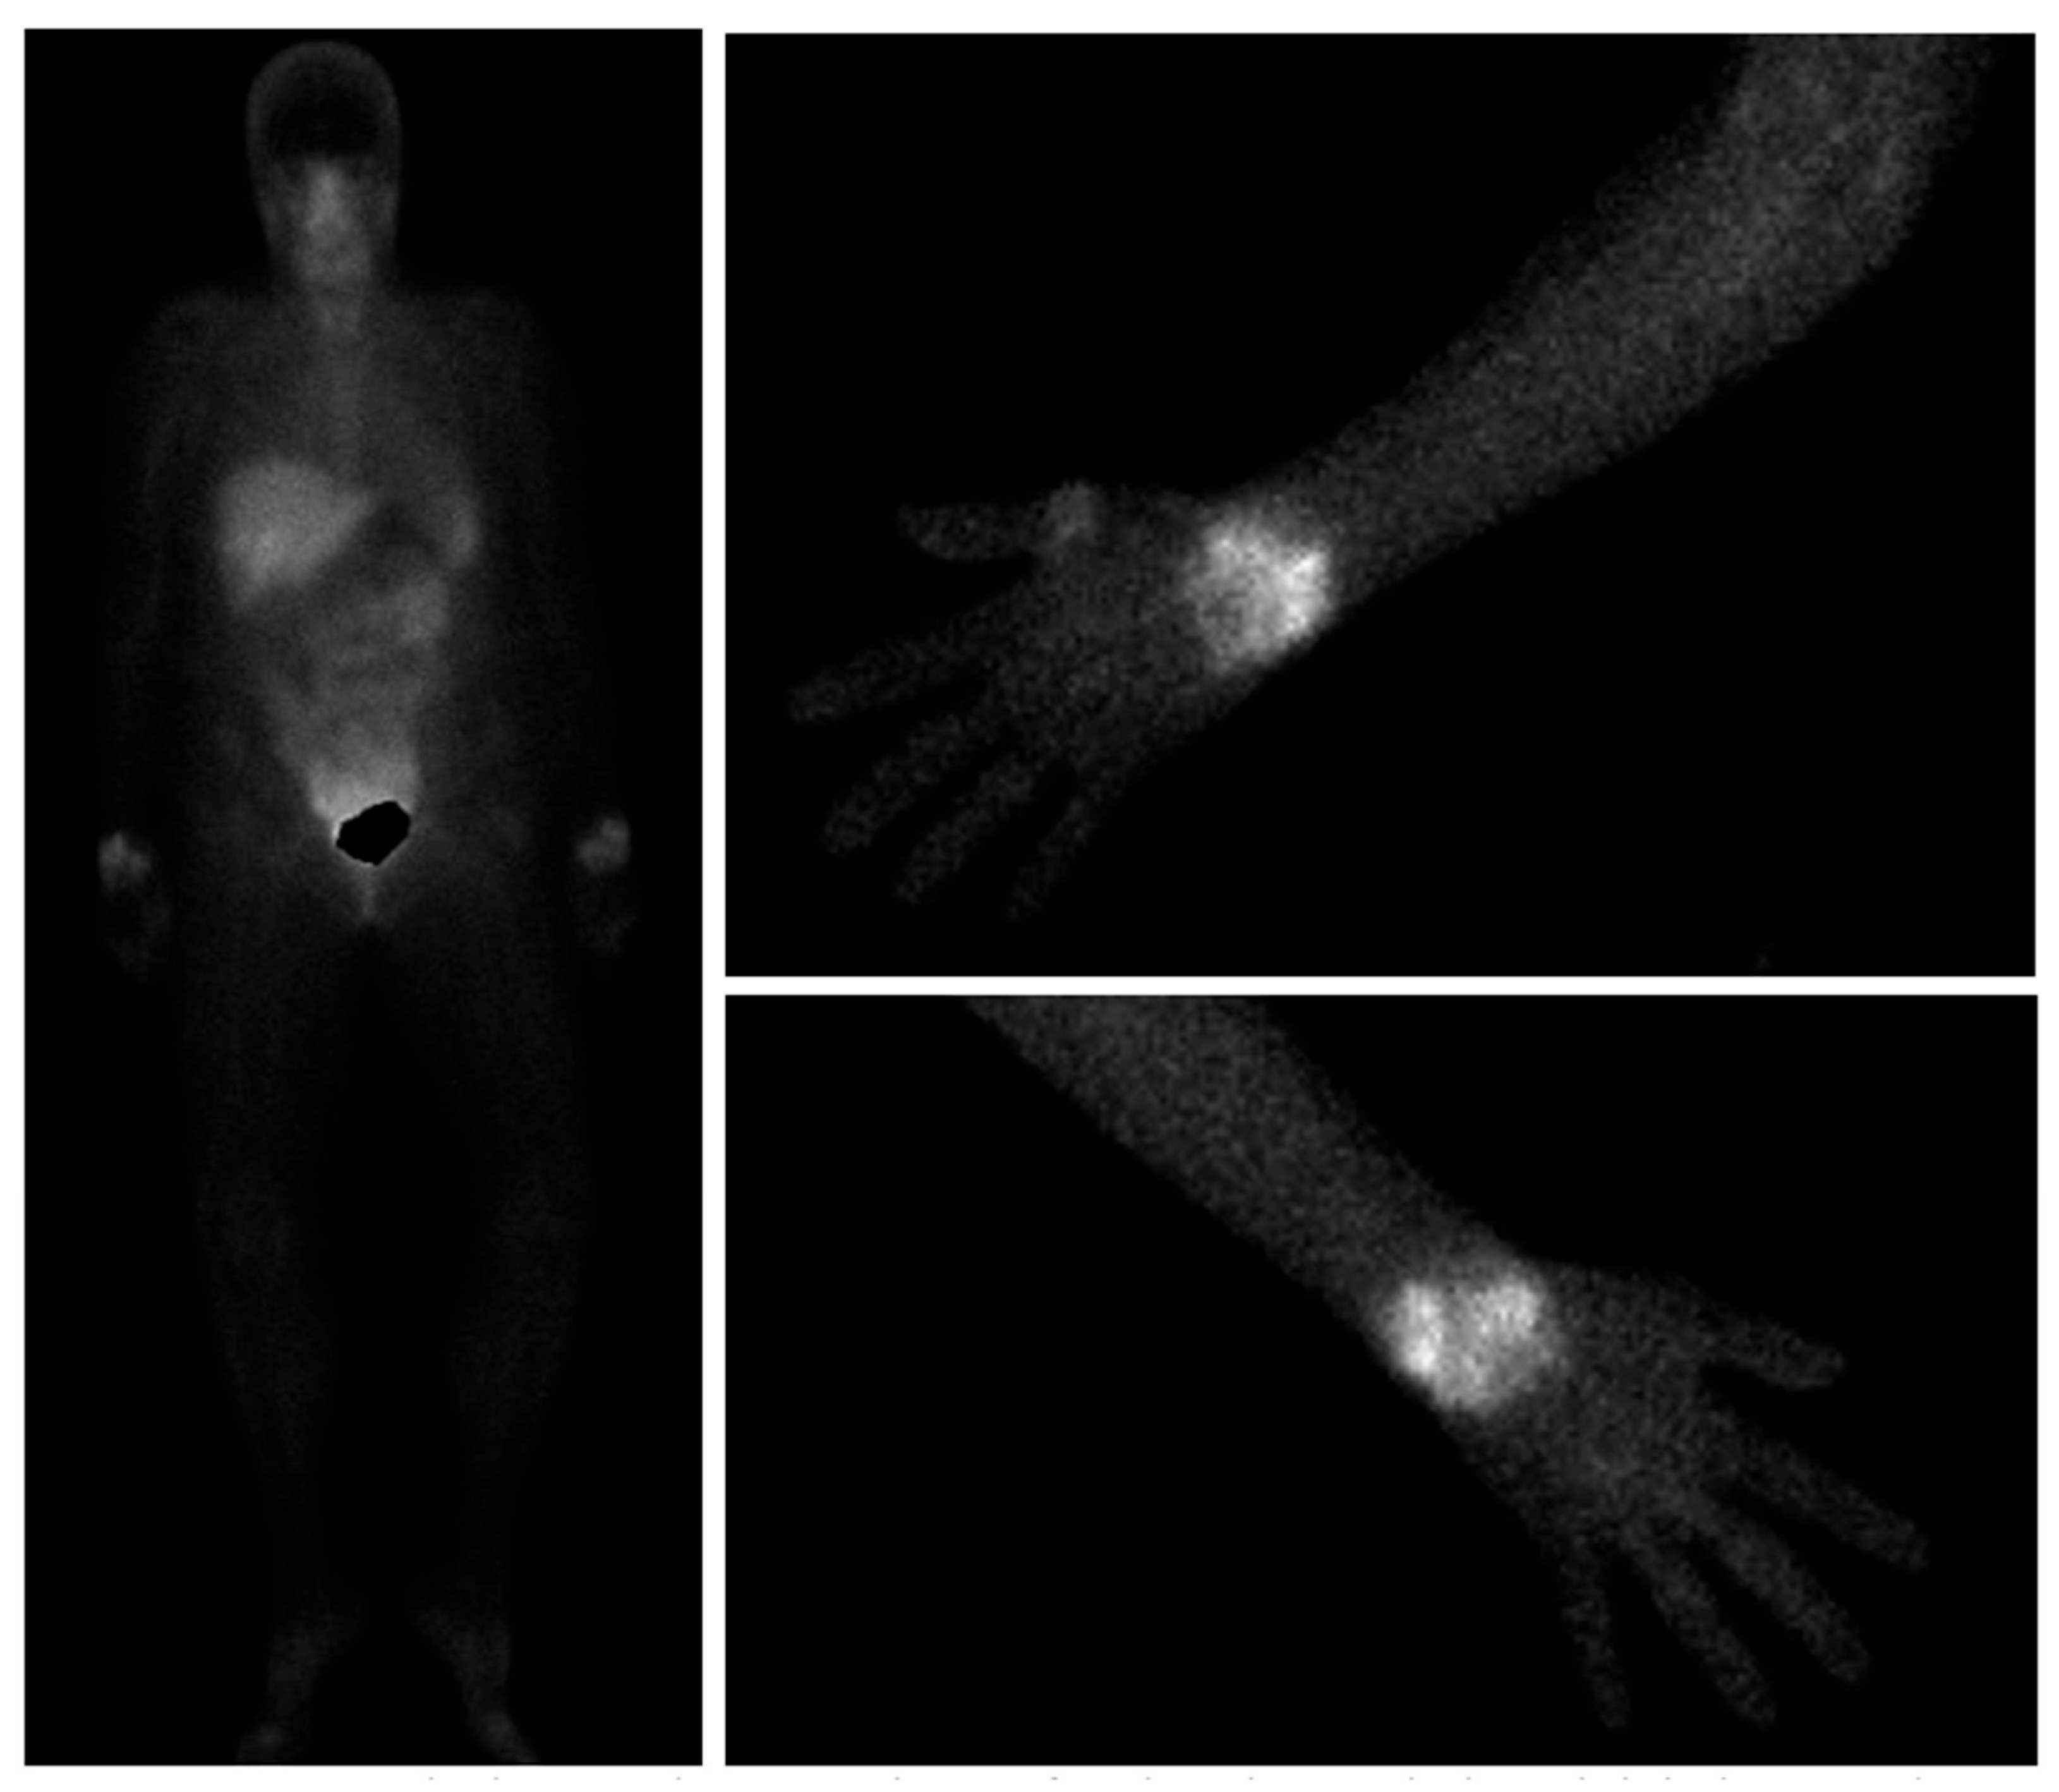

- Imaging Neoangiogenesis in Rheumatoid Arthritis II (INIRA II): Whole-Body Synovial Uptake of 99mTc-Maraciclatide Correlates with Power Doppler Ultrasound and Serum Neoangiogenic Biomarkers-ACR Meeting Abstracts. Available online: https://acrabstracts.org/abstract/imaging-neoangiogenesis-in-rheumatoid-arthritis-ii-inira-ii-whole-body-synovial-uptake-of-99mtc-maraciclatide-correlates-with-power-doppler-ultrasound-and-serum-neoangiogenic-biomarkers/ (accessed on 30 May 2025).

- Cobb, R.; Cook, G.J.R.; Reader, A.J. Deep Learned Segmentations of Inflammation for Novel 99mTc-maraciclatide Imaging of Rheumatoid Arthritis. Diagnostics 2023, 13, 3298. [Google Scholar] [CrossRef]